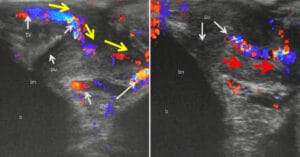

Проблеми часто пов'язані з кровоносними судинами. Наприклад, варикозне розширення вен на яєчках (варикоцелі) може викликати набряк, біль та безплідність. Одне яєчко може болісно скрутитись, а потім перестати отримувати належне кровопостачання. Якщо це станеться, частина тканини яєчка може відмерти. Проблеми з ерекцією часто виникають через хронічне ушкодження кровоносних судин пеніса.